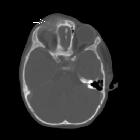

Wilms tumoru

with bony-mandibular, rib and calvarial metastases. Lytic lesion in right frontal bone with soft tissue.